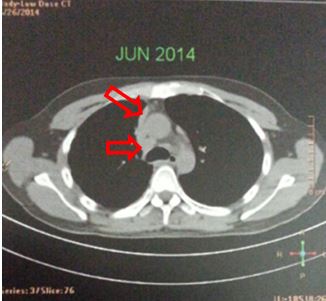

Hình ảnh PET/CT sau 3 đợt điều trị duy trì với Pemetrexed: các khối di căn và hạch không phát triển, max SUV có xu hướng giảm.

Nhiều nốt mờ dải rác phổi phải, màng phổi, max SUV = 4,25. Hạch cạnh khí quản 1,5 cm, max SUV = 4,93 (đầu mũi tên đỏ)

Hình ảnh PET/CT sau 3 đợt điều trị duy trì với Pemetrexed: các khối di căn và hạch không phát triển, max SUV có xu hướng giảm.Hình ảnh PET/CT sau 8 đợt hóa chất: nhiều nốt mờ dải rác phổi phải, màng phổi, max SUV = 4,7. Hạch cạnh khí quản 1,5 cm, max SUV = 6,4